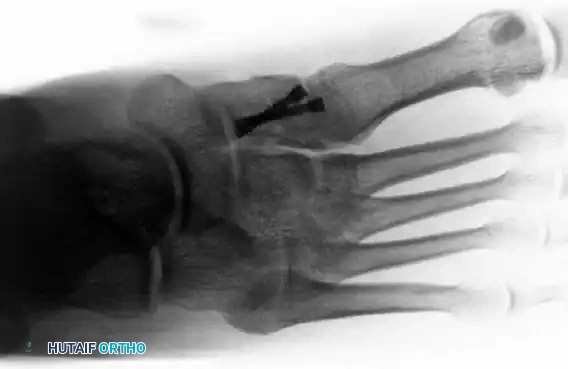

FIGURE 3: Postoperative anteroposterior radiograph demonstrating anatomic reduction and internal fixation utilizing solid cortical screws across the medial and middle columns.